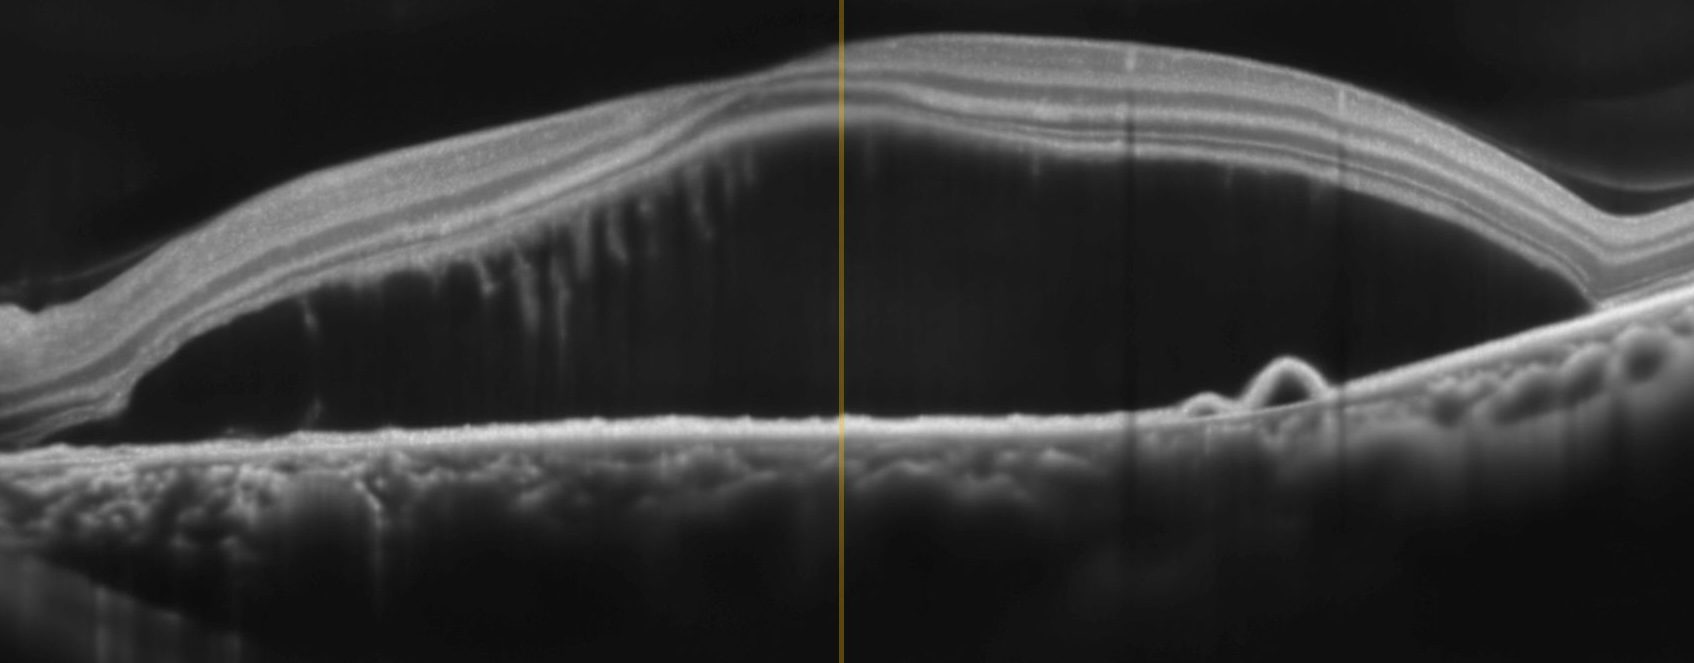

Accurate diagnosis is the foundation of successful retinal care. Our centre is equipped with the latest imaging modalities to detect and monitor retinal diseases with unparalleled precision.

Together, these imaging systems allow us to detect diseases early, plan accurate treatment, and track response to therapy effectively.

OCT scan, Retinal Photography, FFA, and B-Scan.

Diabetic Retinopathy, Retinal Detachment, Macular Hole, ERM, Vitreous Hemorrhage.